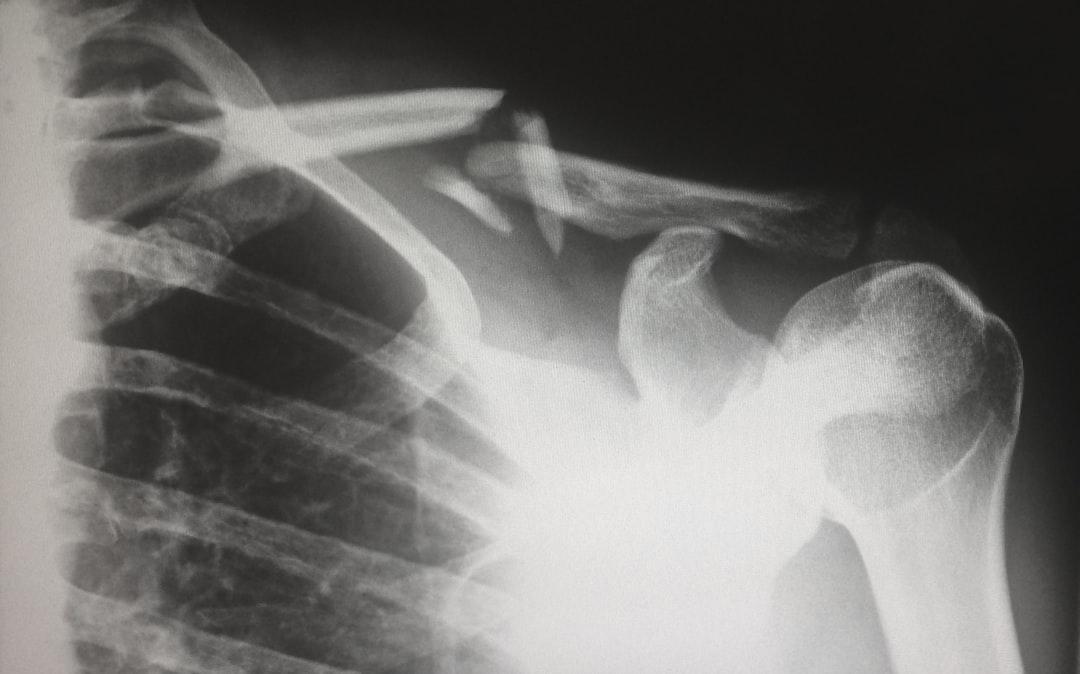

Utredning av axelskador inleds ofta med en klinisk bedömning och kan kompletteras med bilddiagnostik som MR eller ultraljud, särskilt vid misstanke om skador på rotatorcuffen eller andra strukturer i shoulder. Valet av diagnostisk metod kan bero på patientens symptom och skadans art.

När det handlar om att diagnostisera axelskador finns det olika metoder som kan användas för att få en noggrann bedömning av skadans omfattning. I denna bloggsektion kommer vi att utforska två huvudsakliga metoder som används för att diagnostisera axelskador: Användning av MR för exakt bedömning och Vad en MR avslöjar som andra metoder inte kan.

Användning av MR för exakt bedömning

MR ger detaljerade bilder av axelleden och är särskilt användbart för att utreda skador på rotatorcuffen och andra mjukdelar. En av de mest avancerade metoderna för att diagnostisera axelskador är genom användning av magnetisk resonanstomografi (MR). Genom att skapa detaljerade bilder av axeln kan läkare få en djupgående förståelse för skadans natur och omfattning. MR ger en exakt bedömning av eventuella skador på vävnader, ligament och muskler i axeln, vilket är avgörande för att planera rätt behandling. Dessutom möjliggör MR även en bedömning av eventuella inflammationer och andra mjuka vävnadsskador som kan vara svåra att upptäcka med andra metoder.

Vad en MR avslöjar som andra metoder inte kan

MR-tekniken kan avslöja skador som andra diagnostiska metoder kanske inte kan upptäcka. Till skillnad från röntgen, som främst visar benstrukturer, ger en MR också information om mjuka vävnader som muskler och ligament. Detta gör det möjligt att upptäcka mindre skador eller inflammatoriska tillstånd som annars kan gå obemärkt förbi. Genom att använda MR för att diagnostisera axelskador kan läkare få en heltäckande bild av skadan och därmed göra mer precisa behandlingsplaner. Det är viktigt att notera att MR även kan vara till nytta för att övervaka läkningsprocessen och utvärdera effektiviteten av behandlingen över tid. MR kan dessutom identifiera skador på teres minor och andra muskler i rotatorcuffen, vilket är avgörande för att planera rätt behandling.